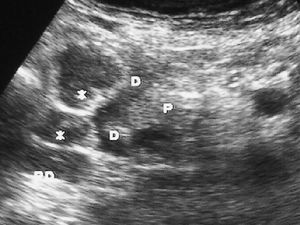

Fig. 9--Diverticulitis duodenal. (A) En la ecografía se observa un divertículo (flechas) con engrosamiento de pared duodenal (D) y alteración de la grasa adyacente (*). (B) Tomografía computarizada de otro paciente con inflamación de divertículo duodenal. Se oberva una lesión quística (punta de flecha) de pared gruesa y borrosa, con material en su interior. P: Páncreas.